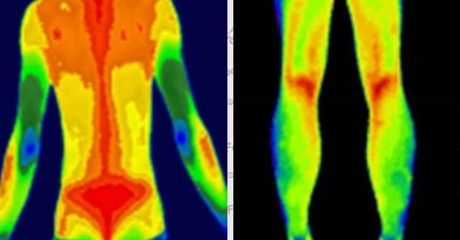

(插入示意圖:脊柱炎癥熱圖 – 紅色熱區(qū)與MRI病灶位置完全吻合)